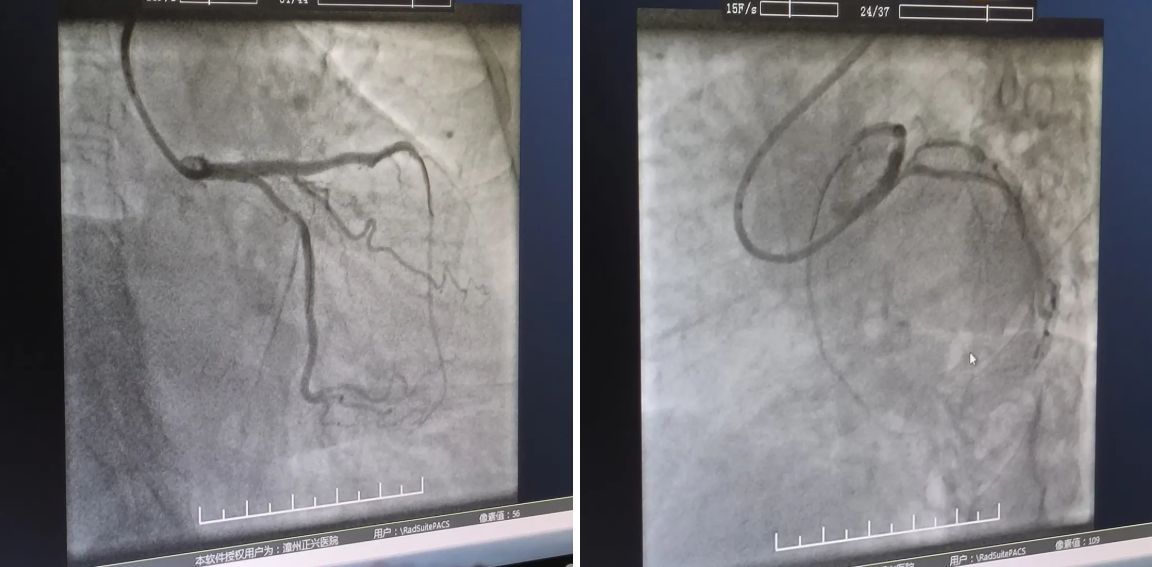

曾丁邻主刀医师与查庆春医师默契配合,迅速完成冠脉造影定位狭窄病变,可见:左主干末端至前降支近段支架以弥漫性偏心性病变,狭窄程度最高达 90%,回旋支开口管状偏心病变,最重狭窄 60%。

『开通前』

术中,介入团队于毫厘之间如穿针引线般将导丝送入狭窄病变处,随即送预扩球囊把左主干-前降支病变扩张开。

看到扩张后病变部位狭窄明显减轻,一鼓作气成功植入一枚支架,医护人员如释重负,解除了一枚「定时炸弹」,悬着的心终于放下了。

紧接着再次精准运用导丝带球囊「进攻」回旋支开口狭窄病变处,一番精细操作下最终顺利打通了血管!经过 2 小时的手术,刘阿姨心肌供血得到改善,如今,康复良好的她也「放心」地出院回家了。

『开通后』